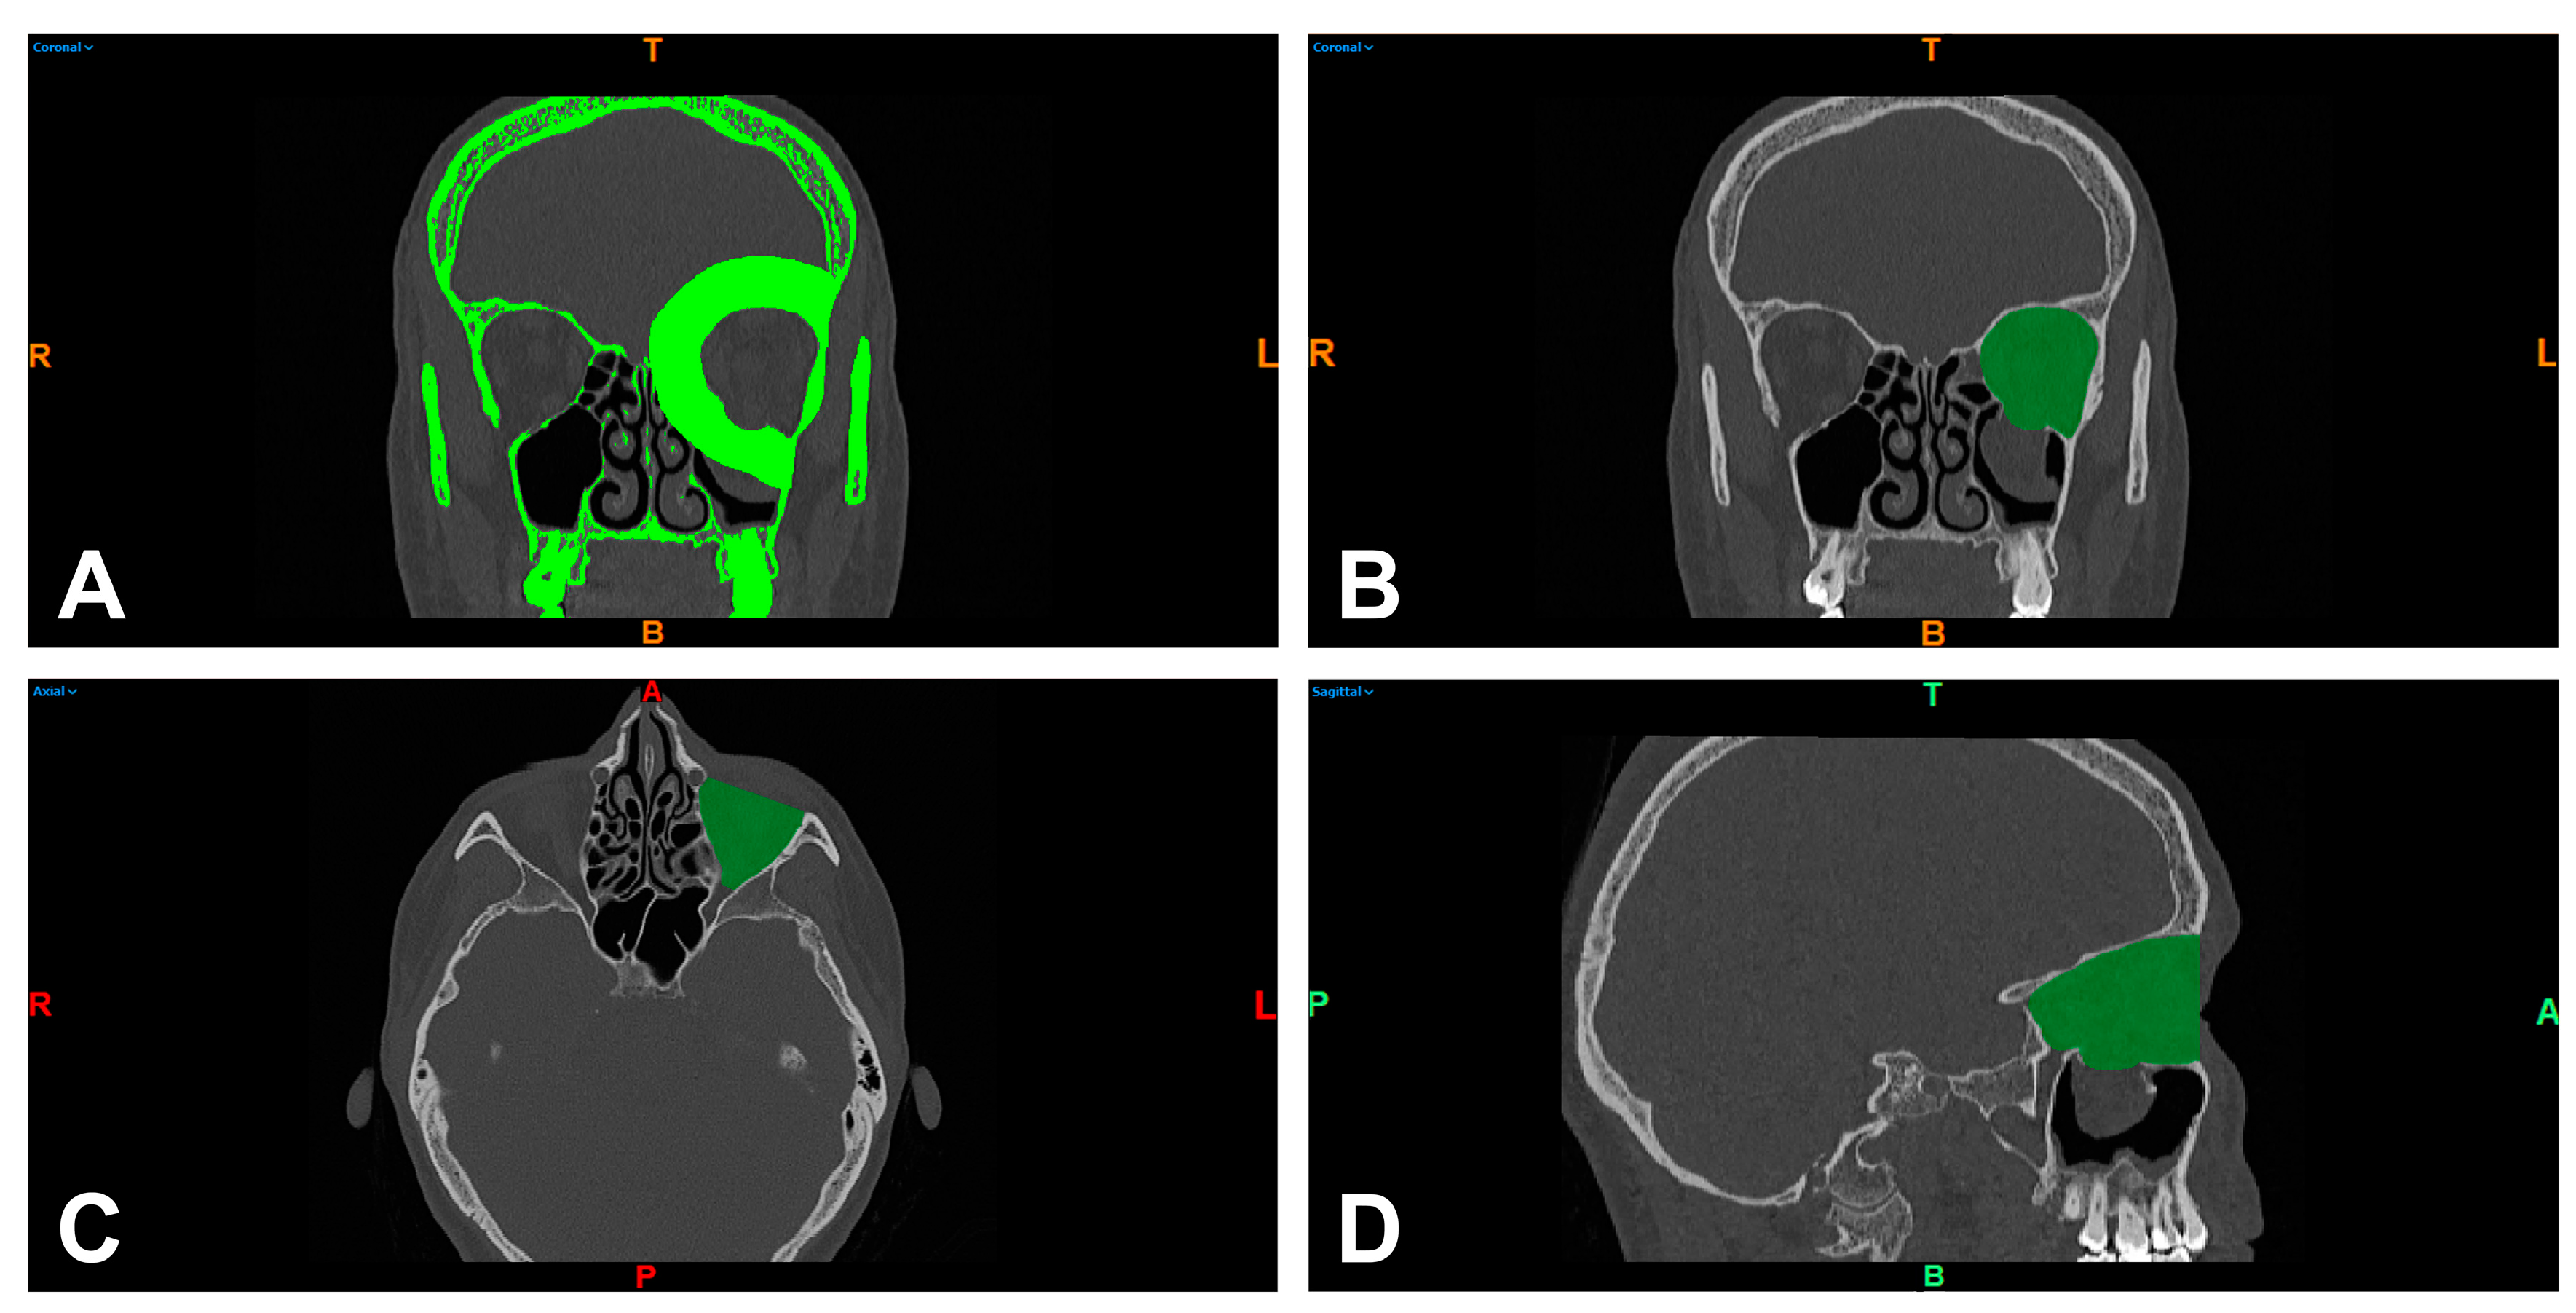

2.2. 3D Model Preparation

2.3. Orbital Volume Measurement